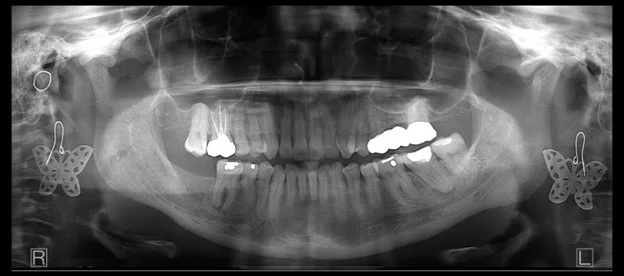

Jewelry

While most operators understand that jewelry should be removed. Sometimes, it’s not understood how much an earring can ruin the entire panoramic radiograph. This is because each earring will show up twice. Once, clearly in the expected location, but then again as a projection, or ghost artifact, typically in the upper posterior.

It is the projection artifact that may not be as obvious, but it can be damaging to the diagnostic value of the radiograph.